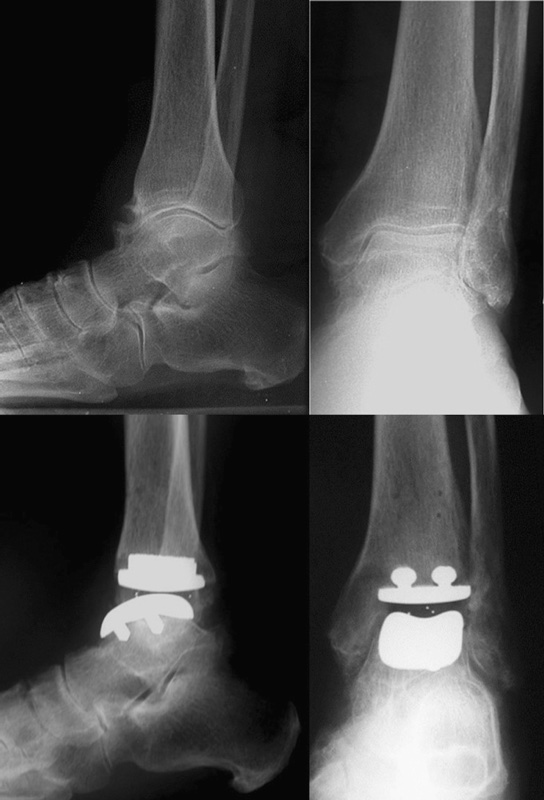

Le protesi di ultima generazione possono essere a 2 o 3 componenti: è sempre presente una componente tibiale e una astragalica, che si articolano attraverso un menisco interposto in polietilene che può essere vincolato alla componente tibiale (protesi a 2 componenti) o libero, interposto tra componente tibiale e astragalica (protesi a 3 componenti, Figura 2)6-10.